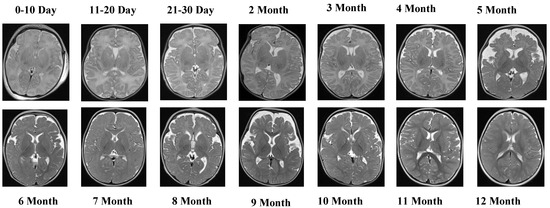

Figure 4 depicts representative MRI slices from the T2 Female sequence, ensuring visual consistency and alignment.

The T2 Female sequence consisted of 6542 images, of which 5233 were allocated to training and 1309 to testing.